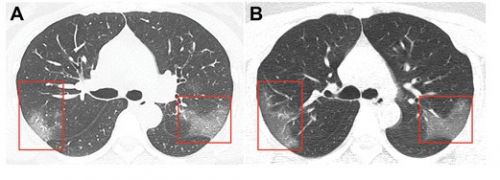

Журнал Radiology опубликовал снимок легких 33-летней китаянки. Женщина была госпитализирована с температурой 39 градусов. На рентгене были множественные помутнения. Через три дня ситуация усугубилась – на втором снимке видно, что область «матового стекла» стала больше.